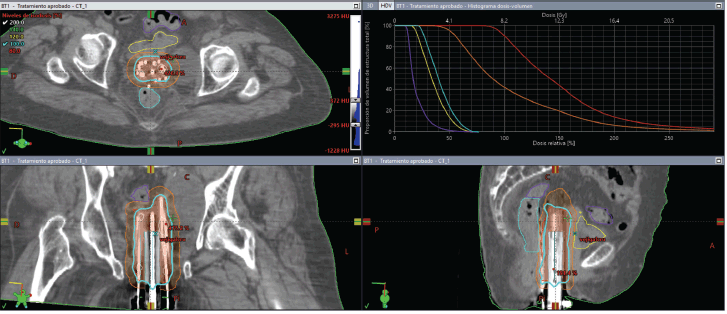

Figure 6. Case 2. PET-CT scan prior to BT. Axial, sagittal and coronal section. A hypermetabolic tumour mass in the vaginal vault and a left pelvic lymphocele were observed.

Figure 7. Case 2. Dose-volume histogram and dosimetric distribution of fraction #1 in axial, coronal and sagittal planes. It is shown in red CTV-HR, in orange CTV-IR, in light blue the rectum, in yellow the bladder and in purple the sigmoid colon.

Total dose was 8.2 Gy × 3 fractions, equating to roughly 48.1 Gy EQD24.5. The plan accounted for prior EBRT (30 Gy in 10 fractions). Although the bladder, rectum and sigmoid colon had some overlap with the new target volume, no dose-limiting constraints were exceeded (Table 1).